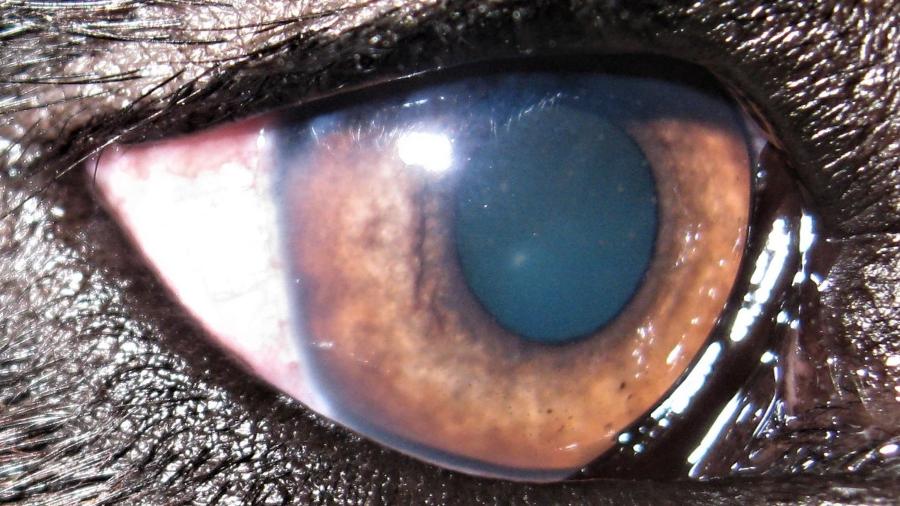

Οφθαλμολογία

Οφθαλμολογία

Το κτηνιατρείο hm vets αναλαμβάνει ψηφιακή ακτινογραφία, έλεγχο δυσπλασίας ισχίου, ορθοπεδική-νευροχειρουργική, χειρουργική μαλακών μορίων, οφθαλμολογία, εσωτερική παθολογία και εργαστηριακές εξετάσεις (αίματος, βιοχημικές, ανοσολογικές, ορμονολογικες, μοριακές και ιστοπαθολογικές).

Το κτηνιατρείο hm vets αναλαμβάνει ψηφιακή ακτινογραφία, έλεγχο δυσπλασίας ισχίου, ορθοπεδική-νευροχειρουργική, χειρουργική μαλακών μορίων, οφθαλμολογία, εσωτερική παθολογία και εργαστηριακές εξετάσεις (αίματος, βιοχημικές, ανοσολογικές, ορμονολογικες, μοριακές και ιστοπαθολογικές).